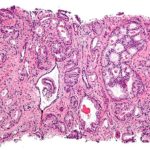

Gli esperimenti sono stati eseguiti con la coltura cellulare SUM149PT, un sistema modello per un tipo particolarmente aggressivo di cancro al seno, cioè il cancro al seno triplo negativo. La chemioterapia è attualmente l’unico trattamento disponibile per questo tipo di cancro.

In collaborazione con il Dr. Gabriele Bonatz delle cliniche Augusta a Bochum (Brustzentrum), la squadra di Hatt ha confermato l’esistenza di TRPV1 nelle cellule tumorali in nove diversi campioni prelevati da pazienti affette da cancro al seno.